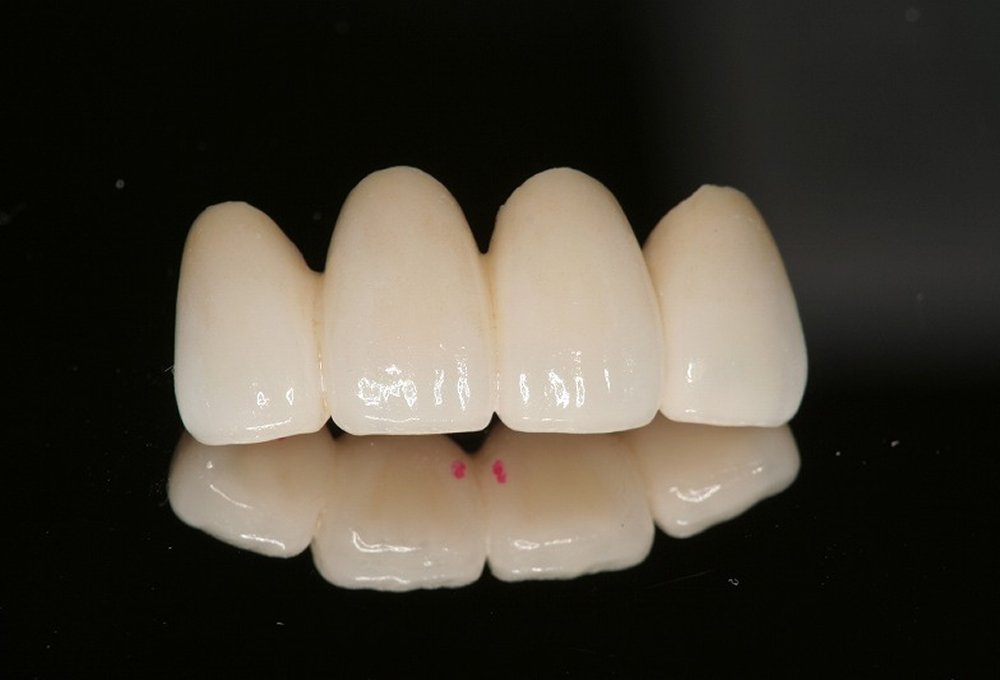

⑧オールセラミック作成